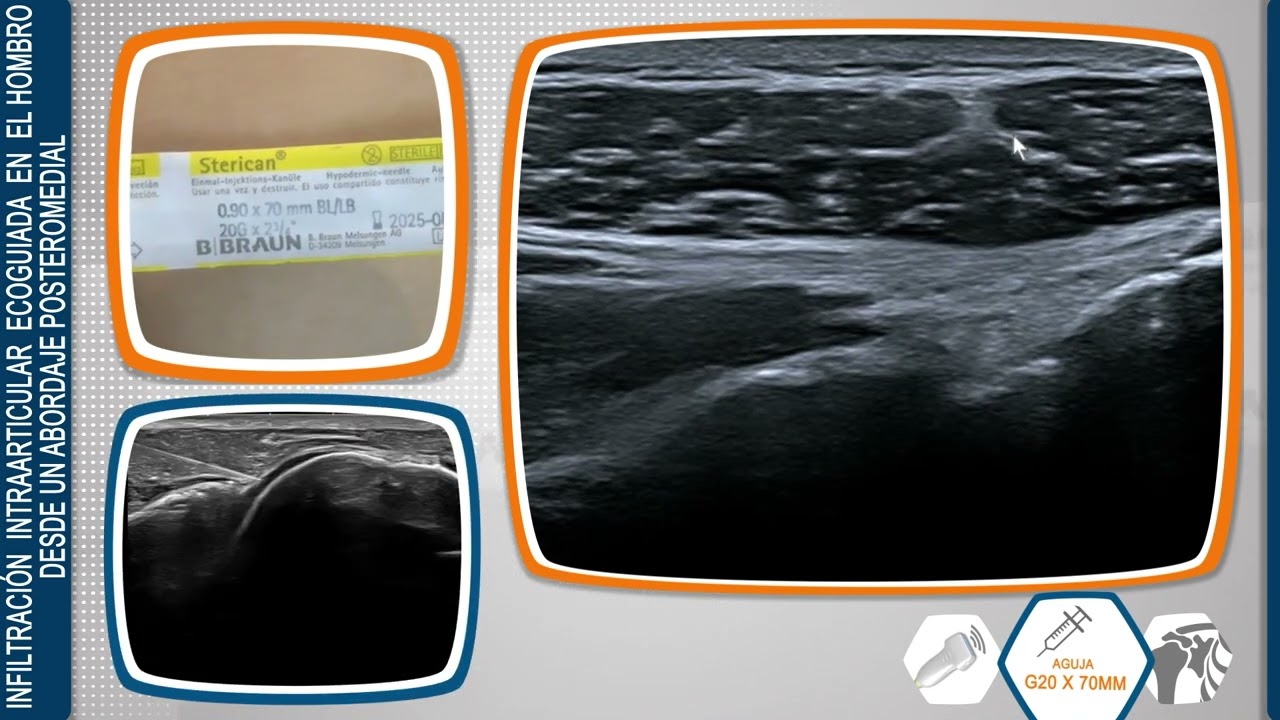

´Técnica de Infiltración Intraarticular Ecoguiada en el Hombro

Dirigido a profesionales sanitarios, el Dr. Javier De la Fuente, de la Unidad de Ecografía Musculoesquelética de Sendagrup, aporta en forma de video las claves para un correcto abordaje de la articulación del hombro.